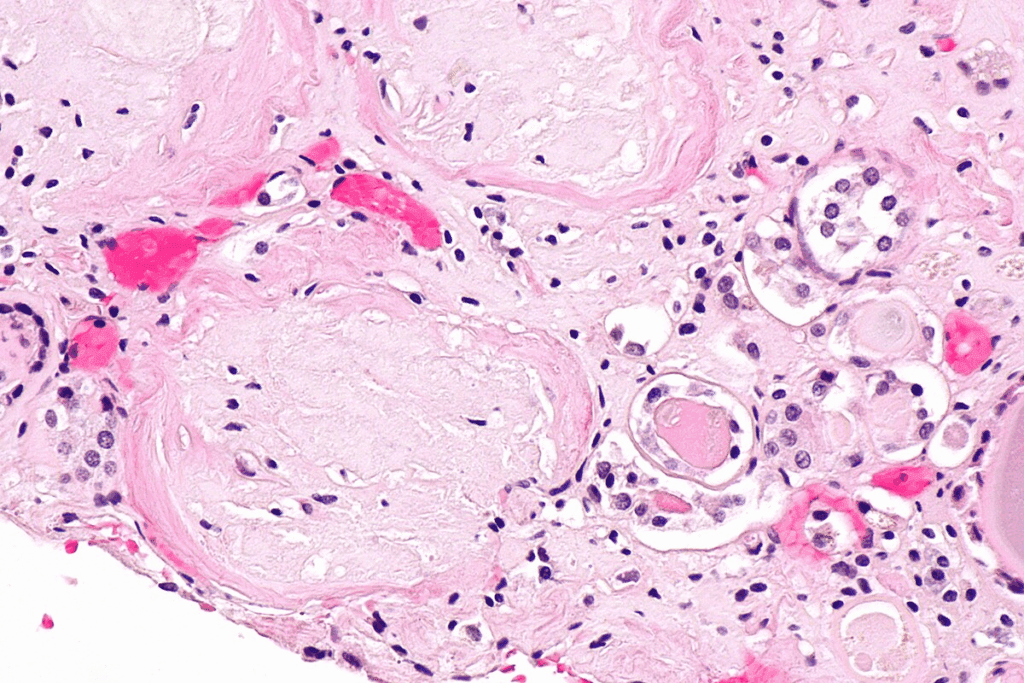

Kidney Biopsy: The Gold Standard

A kidney biopsy is the top way to diagnose glomerular kidney disease. It takes a small piece of kidney tissue for a microscope look. This method gives detailed info on the damage to the glomeruli.

The glomeruli are tiny structures in the kidneys that filter blood. Each glomerulus is a tuft of capillaries surrounded by a capsule. This capsule collects the filtered fluid.

The glomeruli in kidney let small molecules pass through while keeping back larger ones. This is the first step in making urine.